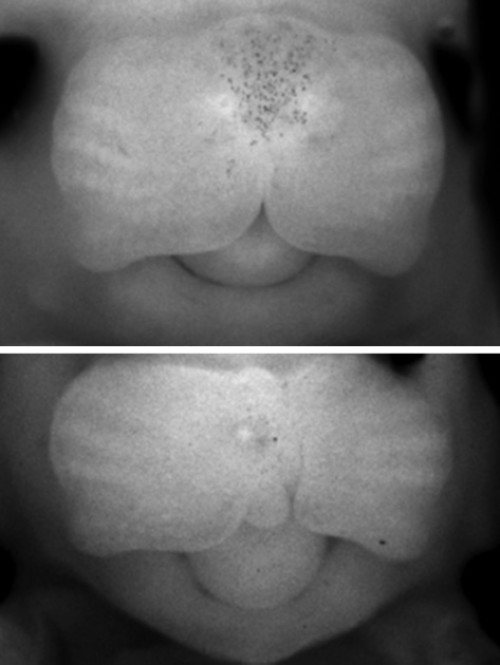

唇腭裂是一个通俗的说法,它是指在人的是唇和颚部有裂口。其实这个名称并不能代表颅面部全部先天畸形。还包括牙槽突裂,另外还有完全性的唇裂还包括鼻底的裂开。再有由于牙槽突裂的存在,还会导致牙齿在发育当中的一个畸形。这种畸形它会影响到口腔和面部的很多的器官和功能。另外由于腭裂存在,还会影响到患者的听力。因此唇腭裂畸形是系统性、可能会影响多个方面的病变。这种病变一般来说是由于在发育过程中,由某种因素而导致形成口腔和面部发育的一些生发中心没有正常的连接和融合所导致的。唇腭裂是一种非常常见的先天的颌面部的发育畸形,一般来说在正常人群里面就达到1-2‰。亚州人群高于非洲人群。或者是600-700个人当中就会有一个唇腭裂小孩的发生。这种唇腭裂会在妊娠前的前三个月就出现,由于各种各样的因素,而影响胚胎的发育。这种畸形会影响到我们小朋友,除了形态和功能以外,它的影响还是非常深远。包括未来的发音,还有颌面部骨骼的发育,还有外形和功能的一些畸形和不正常。还有可能会影响到他参与社会行为,一些社会交往,反过来还会影响他的心理发育。因此这种唇腭裂的畸形是需要我们特别关注的。在胚胎发育的早期,唇、腭是由两侧组织往身体中线融合起来的,若不能正常融合,就会产生各种不同部位的裂缝,单纯嘴唇裂开,称为唇裂,既有唇部裂开又有腭部裂开称为唇腭裂,有时仅口腔内腭部裂开而外部正常,则称为腭裂。

在胚胎发育的早期,唇、腭是由两侧组织往身体中线融合起来的,若不能正常融合,就会产生各种不同部位的裂缝,单纯嘴唇裂开,称为唇裂,既有唇部裂开又有腭部裂开称为唇腭裂,有时仅口腔内腭部裂开而外部正常,则称为腭裂。